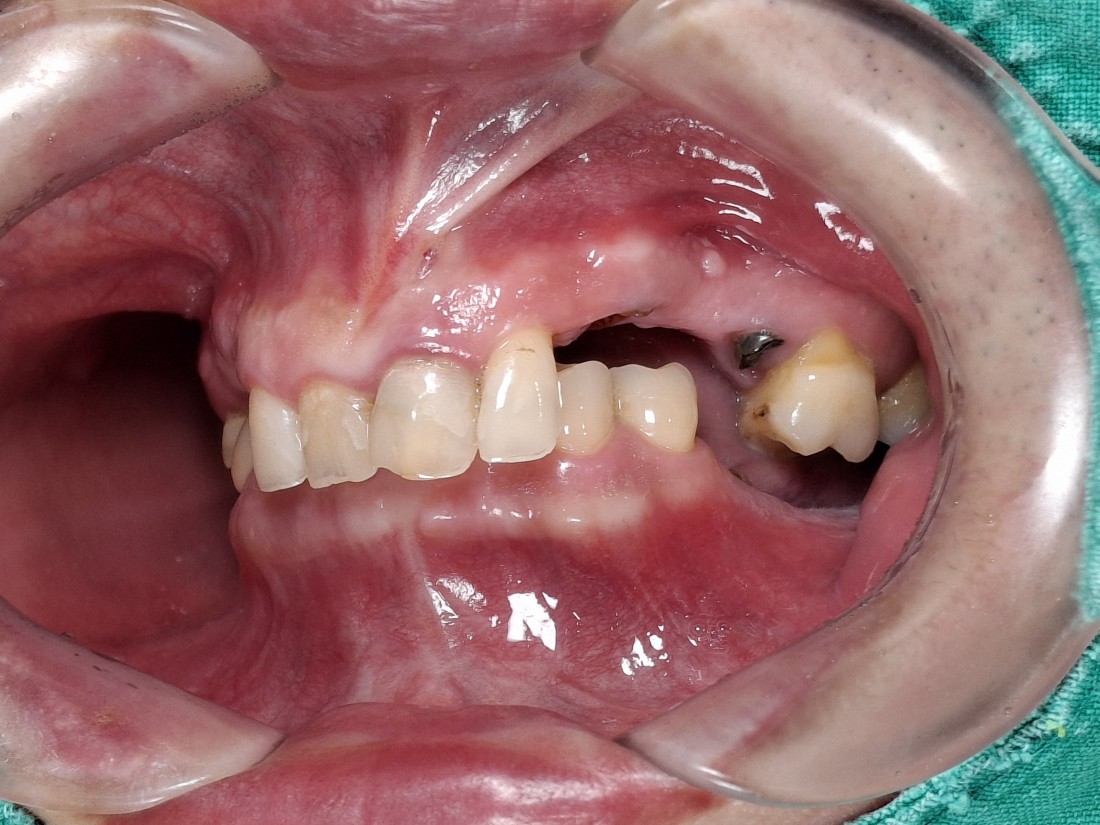

수완동 임플란트 치과는

수 백개의 임플란트 전/후 케이스 사진을

홈페이지에 공유하고 있습니다.

전체 임플란트부터

신경쓰이는 앞니 임플란트,

20대 / 30대 임플란트 케이스부터

80대가 넘는 분들의 케이스까지

정말 다양한 모든 케이스를 보유하고 있습니다.

다양한 각도의 임플란트 식립 전/후 사진으로

실력에 자신있는

수완동 임플란트 치과입니다.